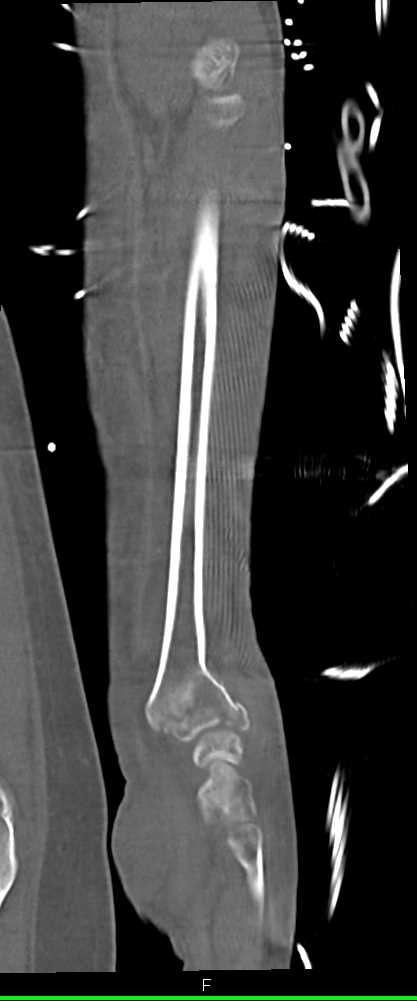

Renal Cell Carcinoma with Bone Metastases and Liver Metastases